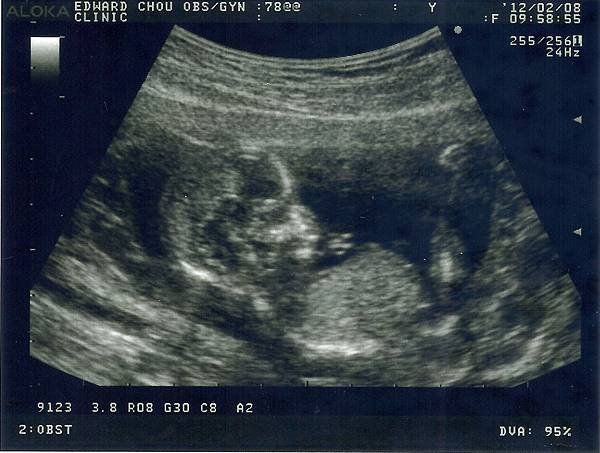

懷孕週數:14W

寶寶啊!把拔馬麻又看到你了哦!你已經滿14週了,小手小腳在馬麻肚肚裡又揮又踢的,很有活力哦!你的頭圍有2.76公分了,頭頂到尾椎也有8公分,醫生伯伯說8+6=14,符合你的週數,所以你有認真長大哦!你的頭圓圓的,會不會跟把拔一樣是個大圓頭呢?要長得跟把拔小時候一樣可愛哦!